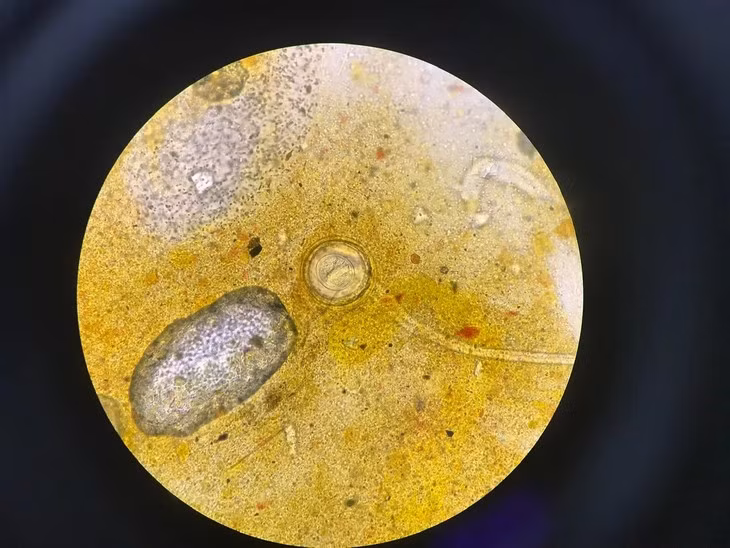

Trứng sán dây chuột trong mẫu phẩm của bệnh nhân khi soi qua kính hiển vi.

Bệnh nhi được gia đình đưa đến Bệnh viện Đặng Văn Ngữ khám sức khỏe. Kết quả xét nghiệm phát hiện có trứng sán dây nhỏ Hemynolepis spp đặc hiệu trong mẫu phân. Bệnh nhi được chẩn đoán mắc bệnh sán dây nhỏ Hymenolepiasis (hay còn gọi sán dây chuột).